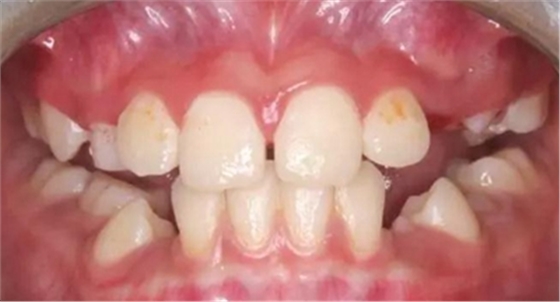

3、牙齦炎癥狀況

(1)檢查牙齦色澤、形態(tài)和質(zhì)地的變化,用文字描述。

(2)用指數(shù)記分法如牙齦指數(shù)(GI)、齦溝出血指數(shù)(SBI)等量化指標來記錄牙齦的炎癥程度。